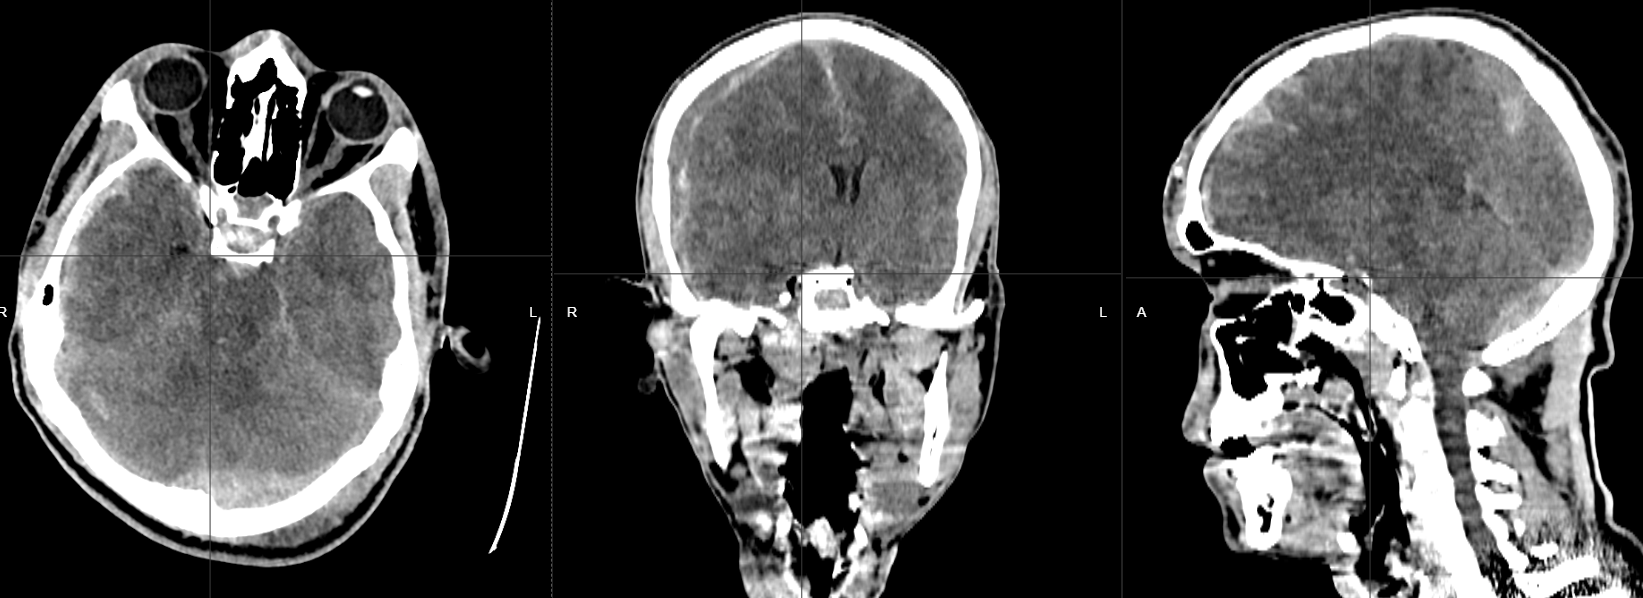

Tomografía cerebral simple en plano axial, coronal y sagital. Se identifica hematoma epidural en fosa posterior izquierda; hematoma subdural en hemisferio cerebral derecho y datos que sugieren edema cerebral.

Paciente de 21 años, masculino, con historia de trauma craneal por accidente vial en motocicleta; con importante deterioro neurológico; al analizar la tomografía cerebral; se identifica hematoma epidural en fosa posterior izquierda, asociada con trazo de fractura; además hay hematoma subdural en hemisferio cerebral derecho, aumento de la densidad de los surcos y cisuras en relación con hemorragia subaracnoidea postraumática, y datos de edema cerebral difuso postraumático.